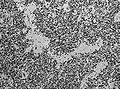

Ependymoma grade II WHO. H&E stain

LM Perivascular pseudorosettes, ependymal rosettes

"Classic" ependymoma

• Rosettes = circular nuclear free zones/cells arranged in a pseudoglandular fashion; comes in two flavours in ependymoma:

• Perivascular pseudorosettes = (tumour) cells arranged around a blood vessel; nuclei of cells distant from the blood vessel, i.e. rim of cytoplasm (from tumour cells) surround blood vessel (nucleus-free zone); more common than ependymal rosette... but less specific.

• Ependymal rosette (AKA true ependymal rosette) = rosette has an empty space at the centre - key feature.

• Nuclear features monotonous, i.e. "boring".[6]

• There is little variation in size, shape and staining.